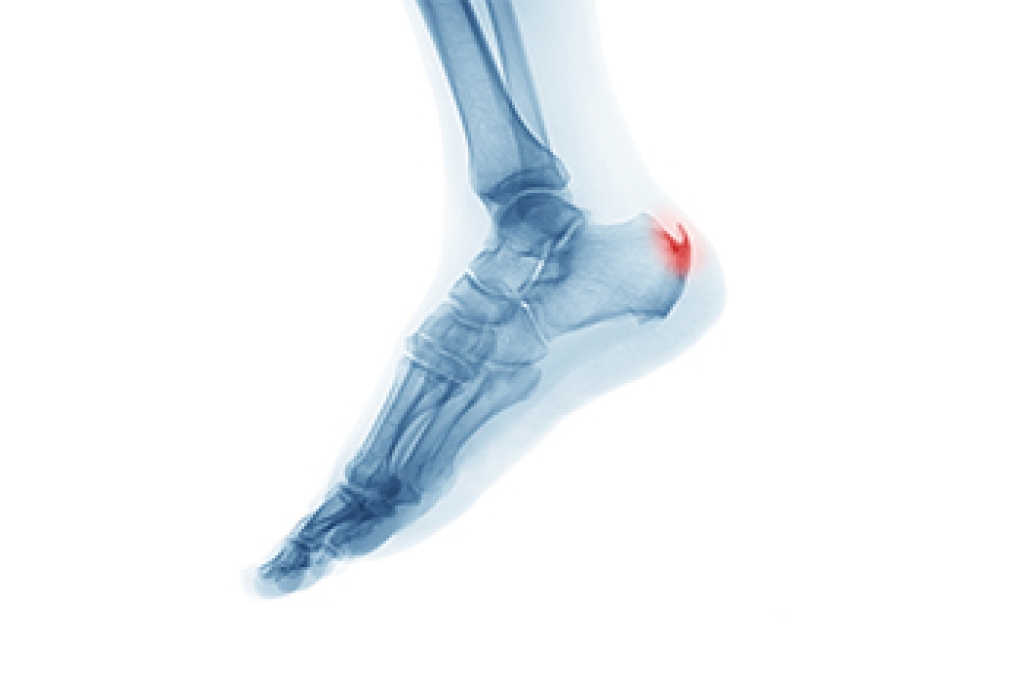

Beneath the skin's surface lies a fascinating framework of foot bones, intricately designed to support our weight and enable movement. Comprising 26 bones, the foot forms three arches that are crucial for balance and shock absorption. However, this intricate structure is vulnerable to various conditions. Fractures can occur due to accidents or stress, while arthritis, an inflammation of joints, can erode bone surfaces. Bunions, caused by misalignment of bones, lead to a bony bump at the base of the big toe. Plantar fasciitis, arising from excessive strain, can cause heel pain. Understanding these conditions empowers us to prioritize foot health. Wearing proper footwear, managing weight, and engaging in a regular exercise routine are vital in preventing foot conditions. If you would like to learn about foot biomechanics, it is suggested that you speak with a podiatrist who can provide you with useful information.

Podiatric biomechanics is a particular sector of specialty podiatry with licensed practitioners who are trained to diagnose and treat conditions affecting the foot, ankle and lower leg. Biomechanics deals with the forces that act against the body, causing an interference with the biological structures. It focuses on the movement of the ankle, the foot and the forces that interact with them.

Understanding biomechanics of the feet can help improve and eliminate pain, stopping further stress to the foot.